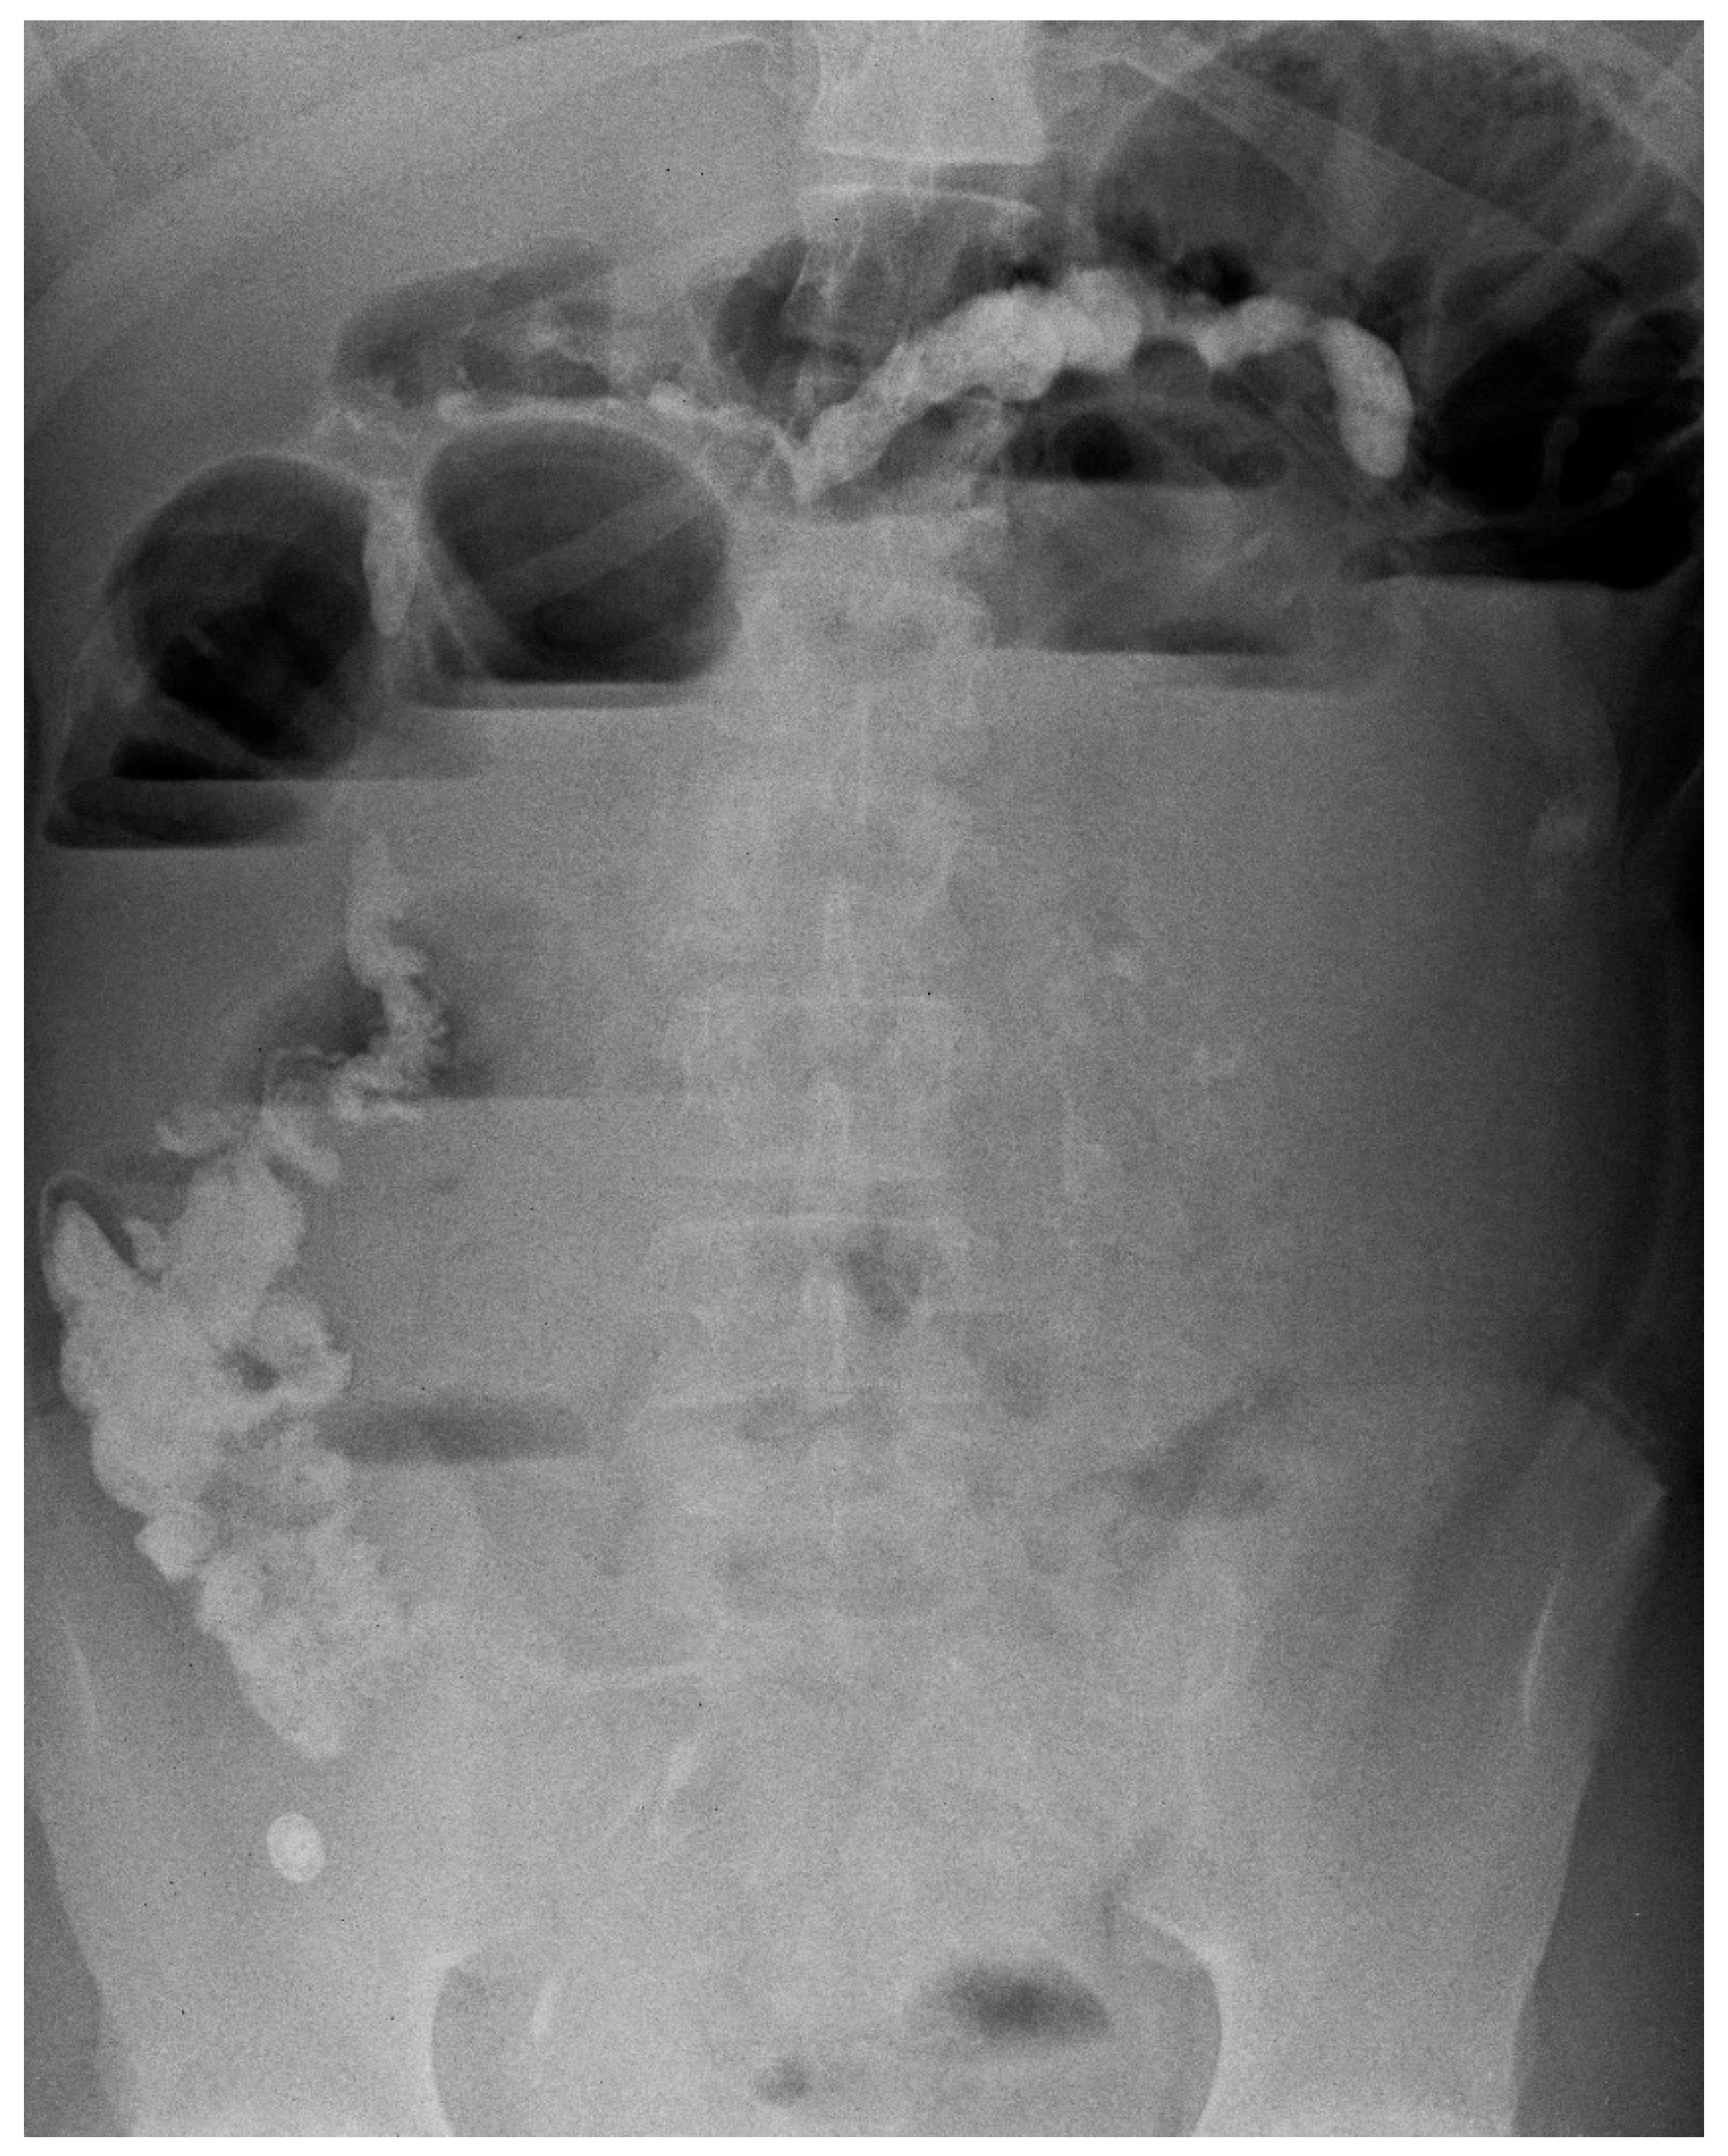

The second patient was a 14-year-old adolescent affected by severe autistic syndrome with ND that presented acute abdominal pain and vomiting. He had a history of recurrent FB ingestions. At the last admission, laboratory tests were unremarkable, and imaging (ultrasounds, US), X-ray) was non-diagnostic. A few days later, the boy was readmitted because of intestinal obstruction with worsening of his clinical picture (Figure 2).

An abdominal CT scan, 12 h after admission, showed multiple FB in the gastric and ileal area. Therefore, he underwent EGDS with the removal of gastric and duodenal FB and residues (sponge, bezoar, plasticized foreign bodies, fishing line). After 72 h, he developed septic shock due to multiple intestinal perforations by FBs and died in the first post-operative day.

Figure 2. Abdominal X-ray and signs of intestinal obstruction.